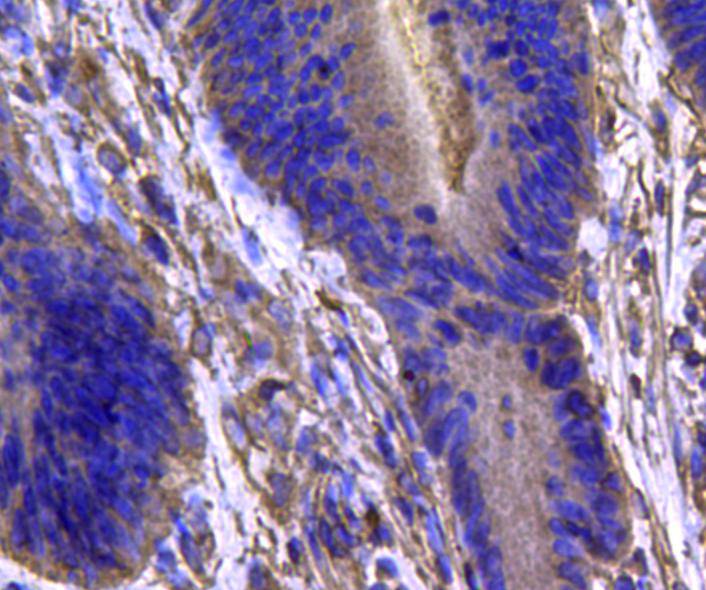

Immunohistochemical analysis of paraffin-embedded human colon carcinoma tissue using anti-IDH1 antibody. Counter stained with hematoxylin.